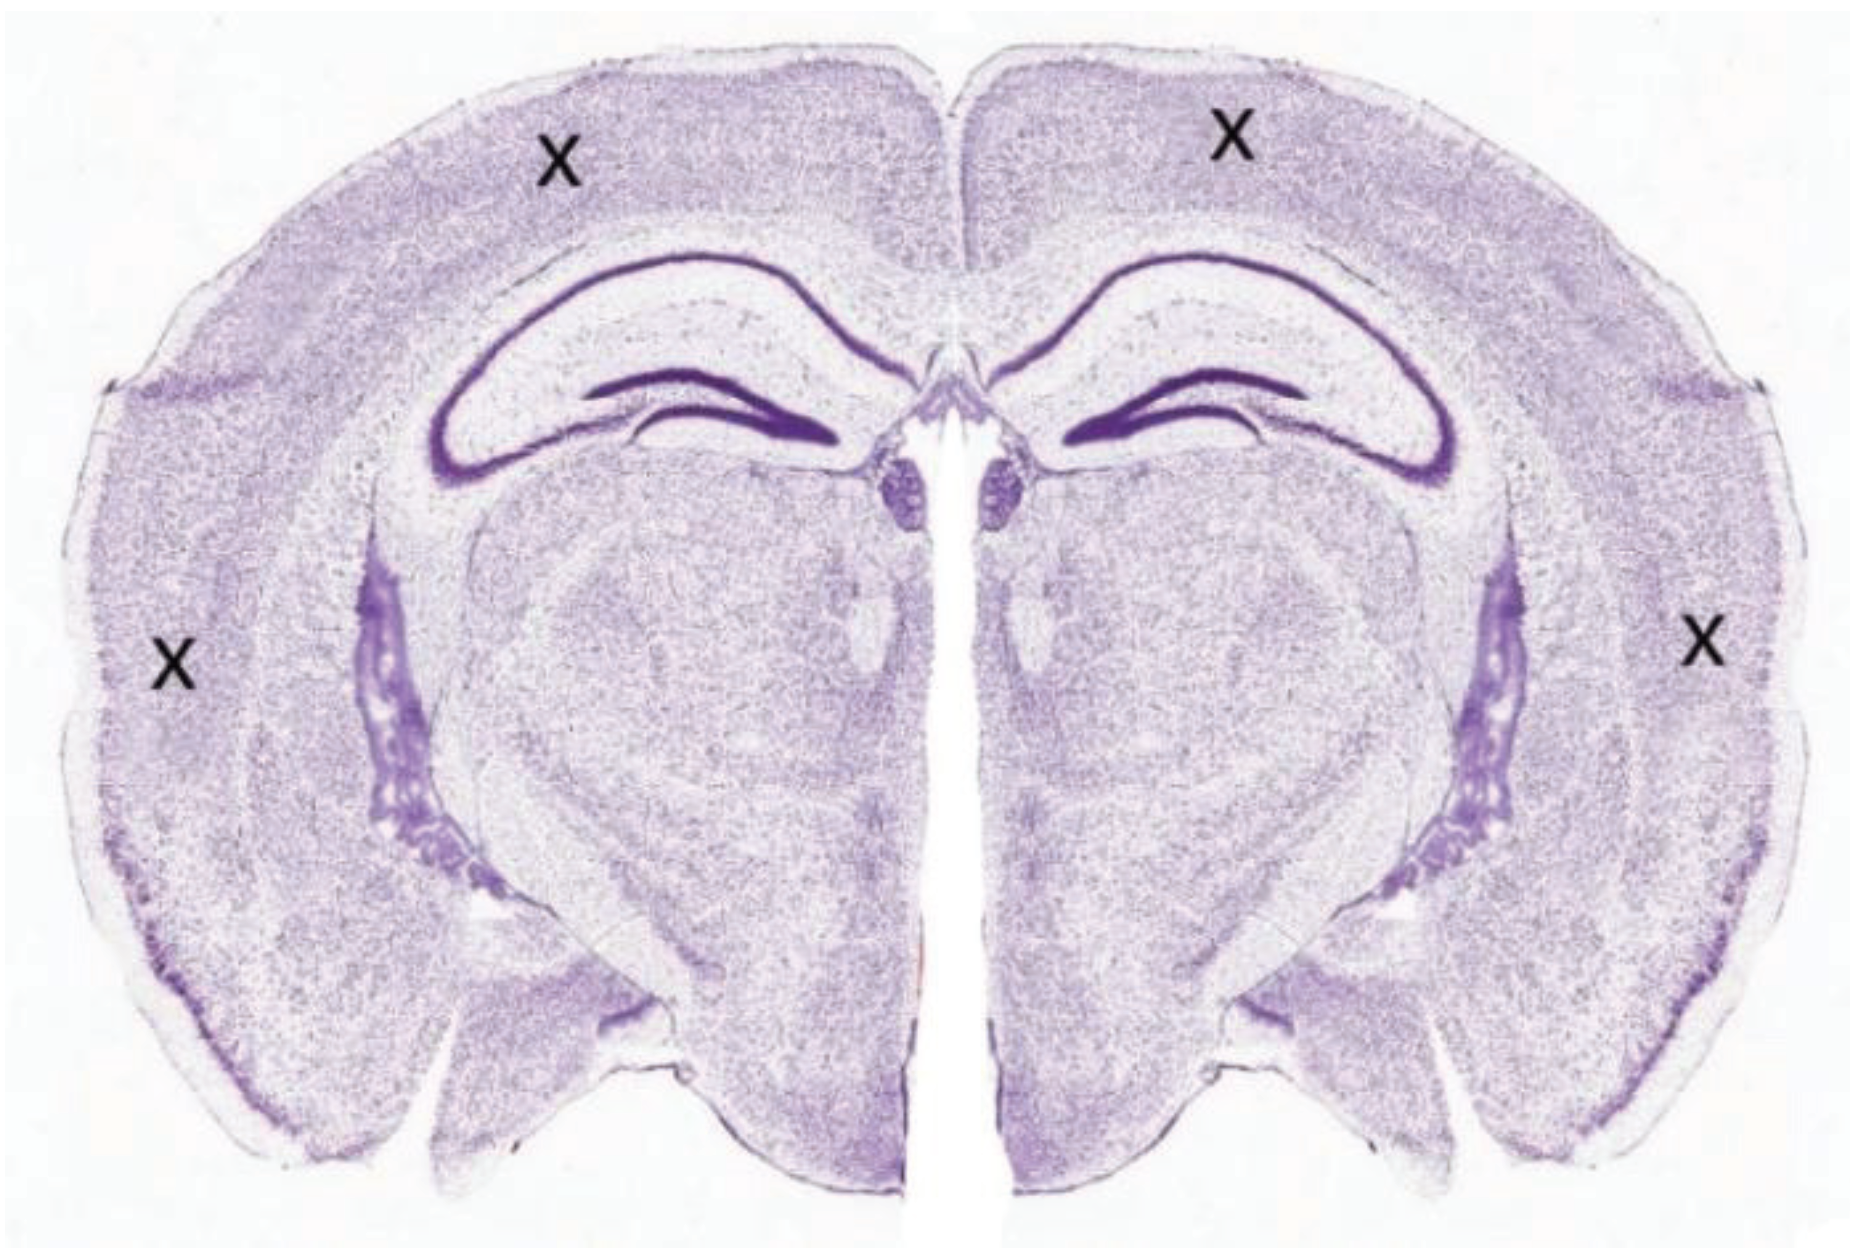

The slices were transferred one at a time to a submersion-style perfusion bath (Kerr Scientific Instruments, Dunedin, New Zealand), which was continuously flowed with no-Mg aCSF at a rate of 5 mL/min. A nylon net was loosely positioned above the slice to stabilize the tissue and help maintain a stable bath solution level. No-Mg SLE activity was recorded using four 75-µm Ag/AgCl electrodes inserted into the cortex, one within each quarter section (Figure 6). A disc Ag/AgCl electrode positioned distant to the slice in the recording bath was used as a common reference/ground. The electrodes were positioned extracellularly to monitor field potential. The analogue signal was amplified (Model 3000 differential amplifier, A-M Systems, Sequim, WA, USA) and converted to a digital signal (PowerLab, ADInstruments, Bella Vista, Australia) for later analysis. The analogue signal was filtered with: high pass—1 Hz, low pass—300 Hz and a notch filter at 50 Hz. The gain was ×1000 and the sampling rate 1000/s.

Figure 6.

Coronal rodent slice showing the approximate recording electrode arrangement (marked by the crosses).